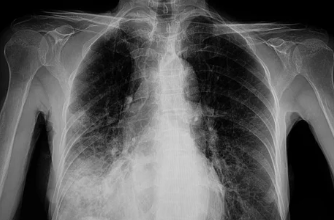

6. 폐렴, 조기 진단과 치료가 중요해요!

폐렴은 조기에 진단하고 치료하면 대부분 완치가 가능합니다. 하지만 방치하면 심각한 합병증으로 이어질 수 있으므로, 기침, 가래, 발열, 호흡 곤란 등의 증상이 있을 때는 병원을 방문하여 진료를 받는 것이 중요합니다.